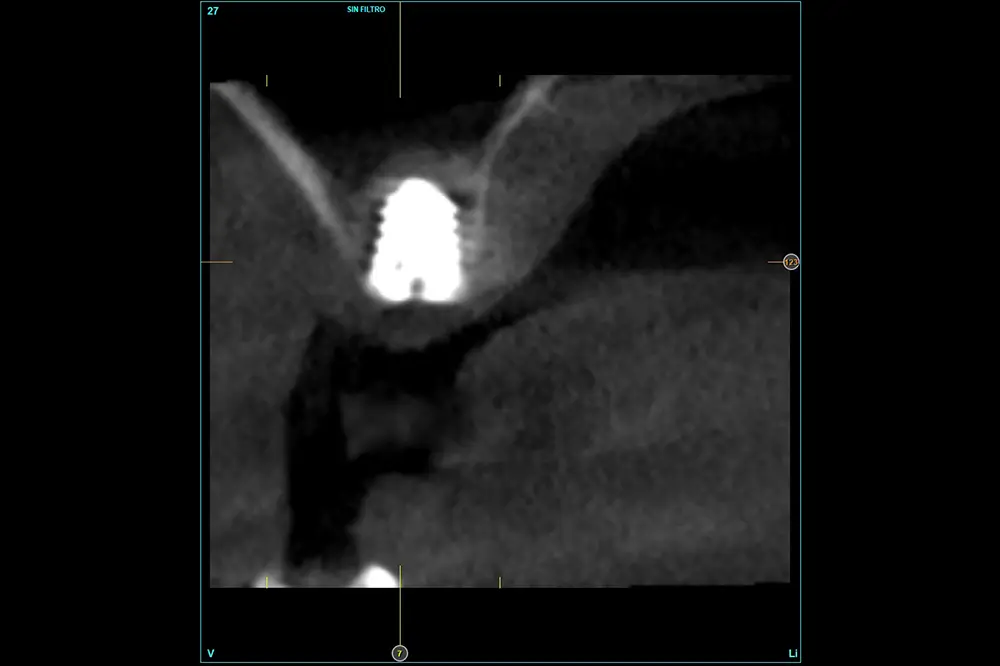

Fig. 9. Cone-beam de planificación donde observamos la escasa altura residual de la cresta a nivel de la pieza 16.

En este caso, la paciente acude con la exodoncia realizada hace dos años de la pieza 16 y una gran atrofia vertical, existiendo únicamente 1 mm en algunas zonas de la cresta, como el área más vestibular, y hasta 3 en la zona más palatina (fig. 9). Procedemos a la realización del fresado tal como se ha descrito en el caso anterior y colocamos el mismo tipo de injerto (autólogo y PRGF- Endoret) y un implante de 4,5 mm de longitud (fig. 10 y 11). Tras la cicatrización a los 4 meses, observamos el aspecto de la zona de la colocación del implante, donde tenemos ahora una altura de 7 mm (fig. 12).